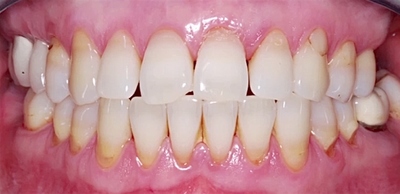

Для течения пародонтита характерны 3 стадии, и симптоматика меняется по мере прогресса заболевания:

- Признаки пародонтита в лёгкой степени совсем незначительны. Дёсны воспалены, в процессе чистки зубов умеренно кровоточат, но без болевых ощущений. Пока не поражена пародонтальная связка, процесс заболевания считается обратимым.

- На средней стадии пародонтита кровоточивость значительно увеличивается, возможны ощущения зуда и жжения. Десна отекает и меняется в контуре, а размер кармана десны доходит до 6 мм.

- Переход в тяжёлую форму пародонтита сопровождается стремительным разрушением костной ткани, зубы теряют опору, веерообразно расходятся и шатаются. На данной стадии заболевания появляется резкий гнилостный запах изо рта, нарушается жевательная функция, и выпадают первые зубы. Глубина кармана десен превышает 6—7 мм.